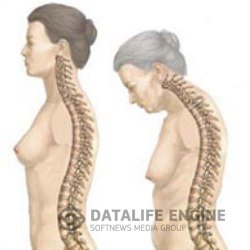

Болезнь БехтереваЭтот недуг считают неизлечимым. Его вызывают дисфункция почек, неполадки в желчном пузыре и печени, протоки... Болезнь БехтереваЭтот недуг считают неизлечимым. Его вызывают дисфункция почек, неполадки в желчном пузыре и печени, протоки...

СпондилезШейный спондилез — хроническое заболевание позвоночника, при котором происходит разрастание костной ткани... СпондилезШейный спондилез — хроническое заболевание позвоночника, при котором происходит разрастание костной ткани...